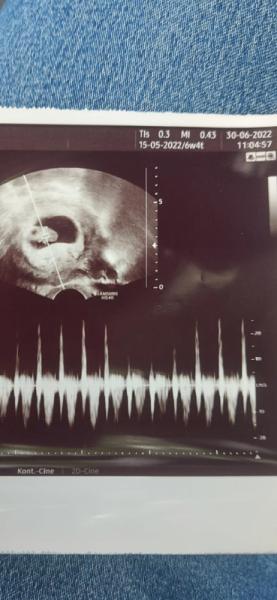

Hallo ihr lieben, vielleicht könnt ihr mir helfen, könnt ihr auf dem Bild die Plazenta finden? Es handelt sich um eine Vaginale Aufnahme. Junge oder Mädchen das ist die Frage Danke euch

Bild zu Ramzi Methode - Schwanger - wer noch? Rund um die Schwangerschaft

lt Ramzi Mädchen - aber bitte nicht drauf versteifen / verlassen